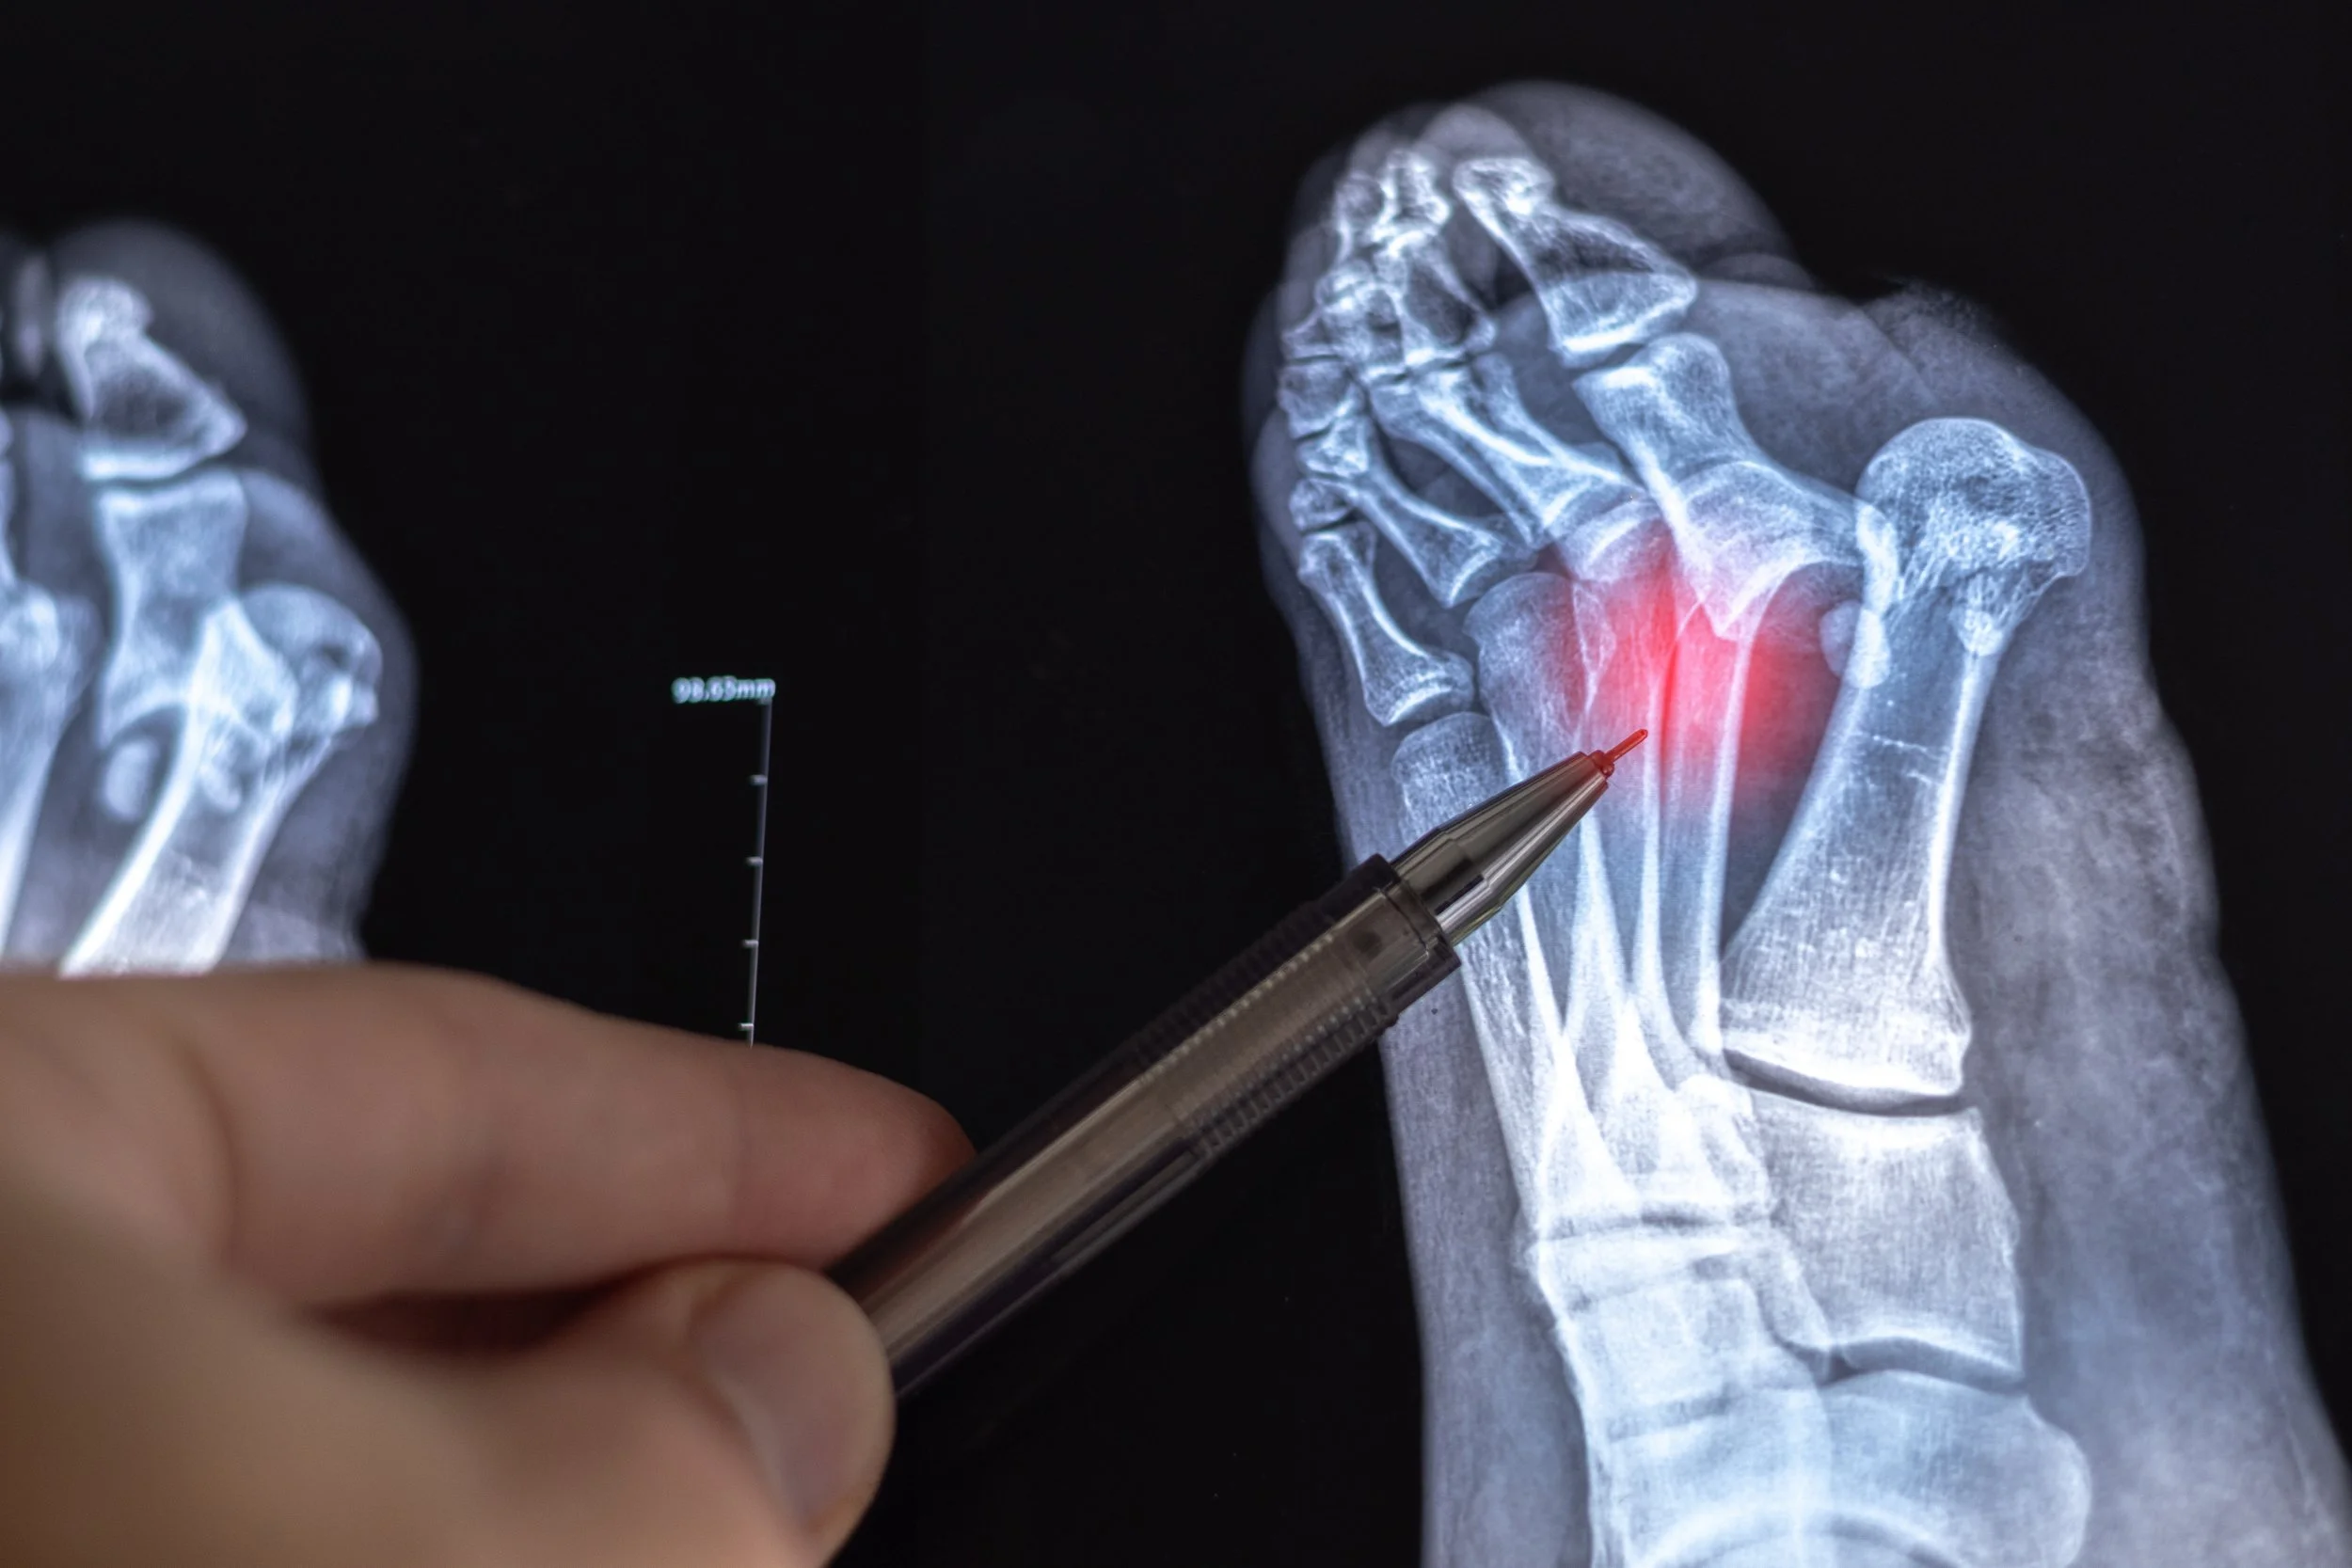

Joint pain and arthritis

Bunions

Hammertoes and other structural deformities

Trauma and fractures